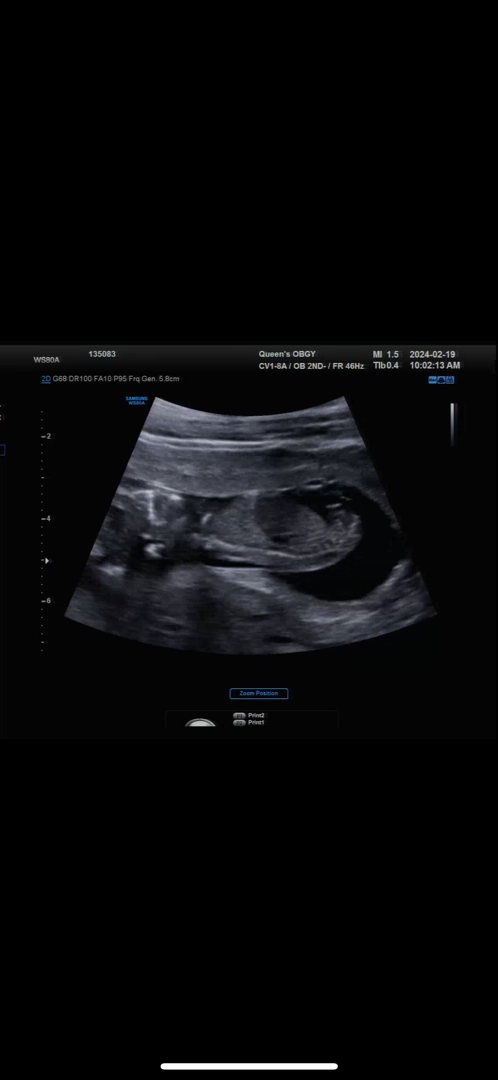

딸일거 같다고 하시긴했는데 각도법 궁금해요😢😢😢 저는 봐도 모르겠네요ㅜㅜ